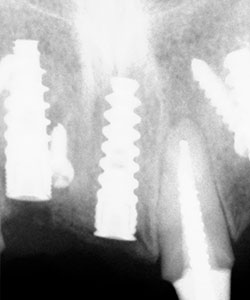

Radiografía Panorámica del paciente, se observa pérdida dentaria y ósea en sector anterior.